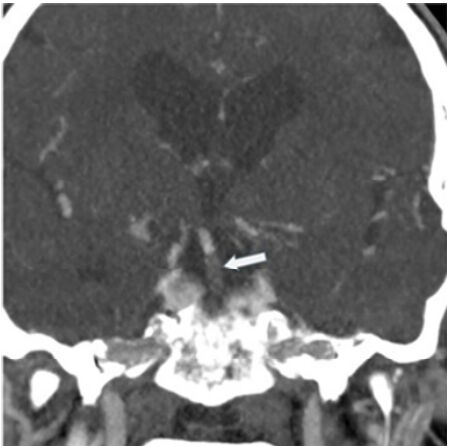

45.下圖箭號所指出血位置為何?

(A)硬膜下腔出血 (B)硬膜外腔出血 (C)蛛網膜下腔出血 (D)腦室出血

46.承上題,下列何者非適當的進一步檢查? (A)CT angiography (B)MR angiography (C)catheter angiography (D)RBC scan for bleeding point